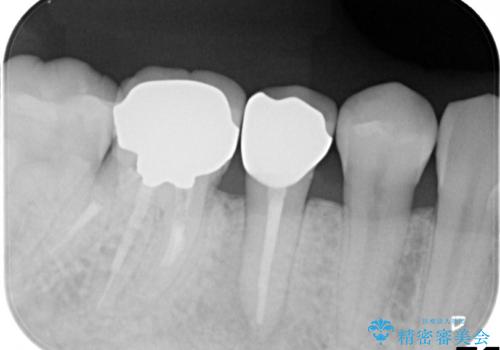

右下5,6間にフィステル(瘻孔)を認めました。デンタルより、右下5根尖に透過像を認め、フィステルに材料を入れてレントゲンにて確認したところ、右下5の根尖に到達しました。

右下5の神経は失活してしまっているため、根管治療の必要性を説明の上、根管治療をした後セラミッククラウンを入れていくこととなりました。